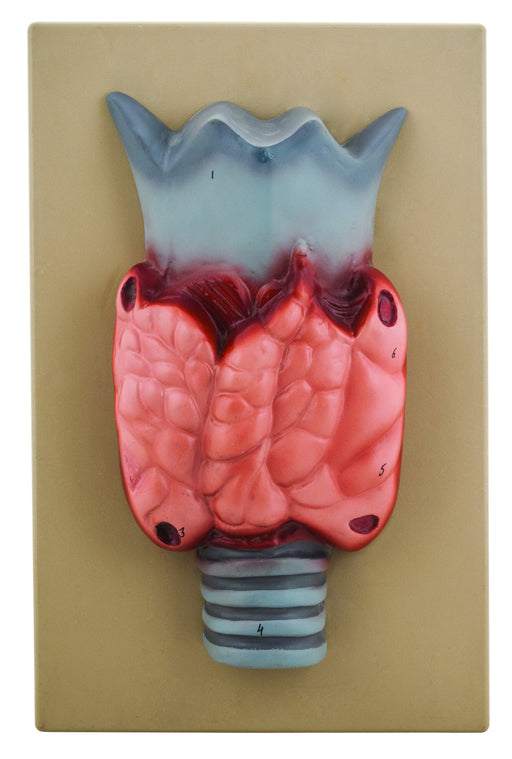

Model Thyroid Gland

Showing magnified view of thyroid gland. Showing magnified view of thyroid gland. Mounted on base. Numbered with English Key Card. Size 38 x 24 x...

View full detailsAM0262 -